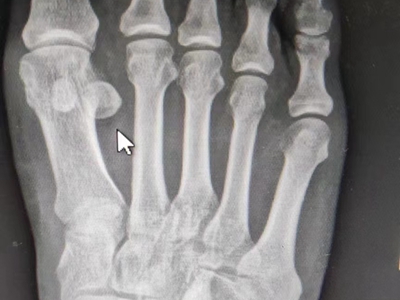

痛风性关节炎好发于40岁以上男性,多见于第一跖趾关节,也可发生于其他较大关节,如踝部关节、膝关节、手指关节等,表现为突然出现的关节肿胀和剧痛,受累关节及其周围软组织明显发红、发热和肿胀,剧痛难忍,以及关节活动受限,伴有痛风石的形成和慢性关节变形。

痛风性关节炎是众多关节炎类型中的一种,是由于血尿酸增高,尿酸盐结晶在关节、滑囊、软骨、骨质或关节周围组织以结晶形式沉积,并引起一系列炎症反应所造成,高嘌呤食物、饮酒、受冷或劳累等因素易诱发痛风。